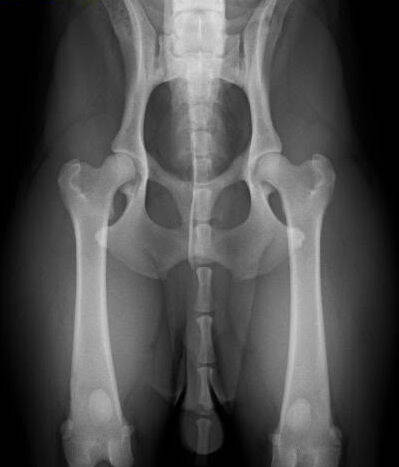

Heupdysplasie (HD)

Heupdysplasie is een ontwikkelingsstoornis van de heupgewrichten, veroorzaakt door zowel erfelijke factoren als milieufactoren. Symptomen zijn moeite met opstaan en kreupelheid aan de achterhand. HD kan worden vastgesteld door het maken van röntgenfoto's van de heupgewrichten. Uitslag HD-A is het beste, HD-E het slechtst.

Een HD foto, resultaat HD A, norbergwaarde 38